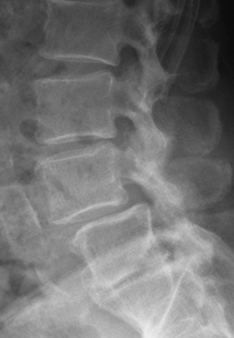

| X射线检查 | 对脊柱的生理弯曲及骨密度侦查的必要检查 |

X射线图像